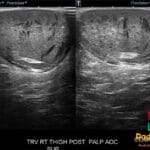

- Radiology Cases: Images with a to-the-point discussion highlighting the specific diagnostic criteria.

- Radiology Case of the Day Collection: Aunt-Minnie Board Cases for Rapid Review.

- Radiology Spotters: 700+ spot / “Aunt-Minnie” cases divided into sets of 10 each!